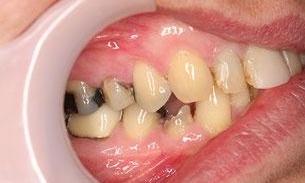

This man in his 50s was unhappy with the amalgam filling used to fix cavities. After discussing options, we agreed to fix his appearance by putting crowns on the teeth which create more of a natural look. This patient was very happy with the end result and is now in maintenance mode.